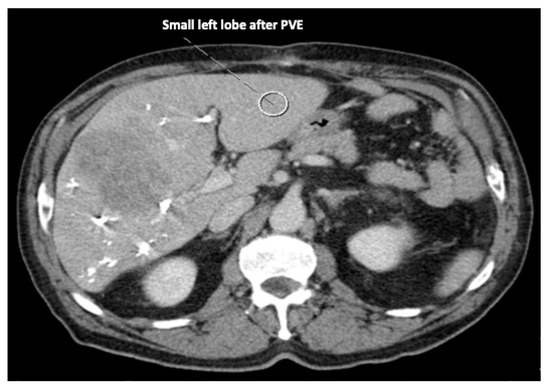

Recent reports have proposed several methods to augment the future liver remnant before extended right resection of the liver [1,2,3,4,5]. Although portal venous embolization is well established and produces satisfactory results in many patients, the growth of segments II and III is often slow and sometimes insufficient in volume (Figure 1 and Figure 2) [6,7]. This precludes many patients from potentially curative resection. The technique of in-situ liver transsection and portal venous division (also referred to as ISLT or ALPPS) and secondary completion hepatectomy, has gained some attention over the past decade to generate faster and more efficient growth of the liver remnant [3,4,5,8]. The technique of this procedure varies. Due to the high complication rate of both procedures, many modifications have been described to minimize the trauma of the first step [9,10,11]. However, a standardized initial operation can be performed safely and reduces the complication rate in the vulnerable phase before the second operation. To obtain optimal growth and to prevent situations that make the completion hepatectomy more urgent, the initial operation has to be designed to avoid bile leaks, venous congestion and segmental liver ischemia. For accurate planning of the two steps of this complex operation, a detailed understanding of the underlying pathology and the anatomy is of major importance. Preoperative imaging will have to identify arterial and venous blood supply and drainage as well as the biliary anatomy. We routinely use computed tomography with a portal and arterial phase. An MRCP is reserved for additional questions regarding the biliary tree. The patient is then presented to and discussed in our multidisciplinary hepatologic tumor board before treatment.

Figure 1. A patient with a multilocular, large hepatocellular carcinoma, a small left lobe that would not suffice to avoid liver insufficiency after resection, and insufficient portal venous embolization.